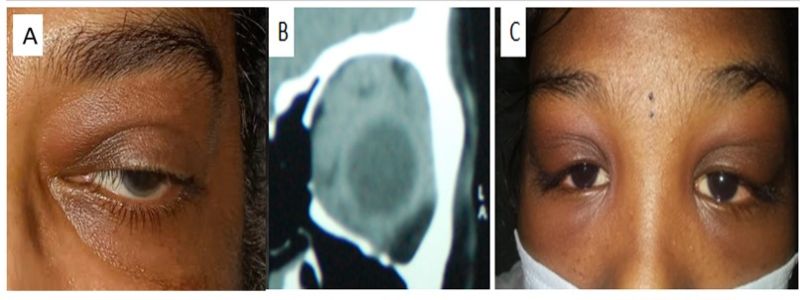

Clinical picture showing lid edema and supraorbital sullness (A),corresponding CT image showing diffuse enlargement of extraocular muscles in a case of idiopathic orbital inflammatory disease (B),clinical picture showing bilateral dacryoadenitis with Sshaped ptosis in both eyes (D).